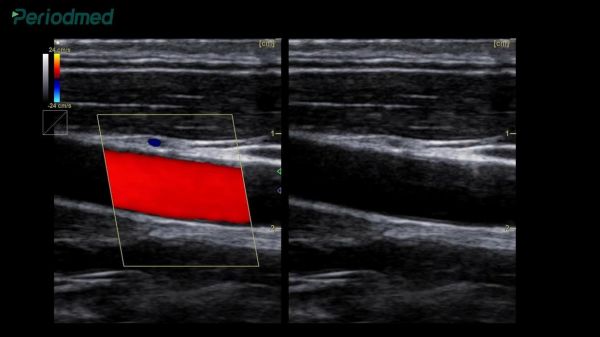

例如,40岁及以上的成年人,若存在消化道肿瘤家族史,应每隔3至5年接受一次胃肠镜检查,这比每年检查肿瘤标志物更为直接有效。同时,高血压和肥胖人群应关注颈动脉超声,及时发现动脉硬化斑块。女性在30岁后应增加乳腺B超检查,必要时在40岁后进行钼靶检查,以更好地预防乳腺癌。